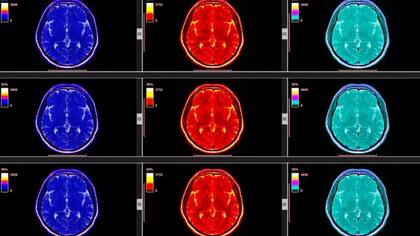

Hacemos experimentos con neuroimágenes para medir la activación de determinadas zonas en el cerebro humano.

Eso nos ha permitido entender que se activan las mismas zonas, aunque sean distintos tipos de placeres.